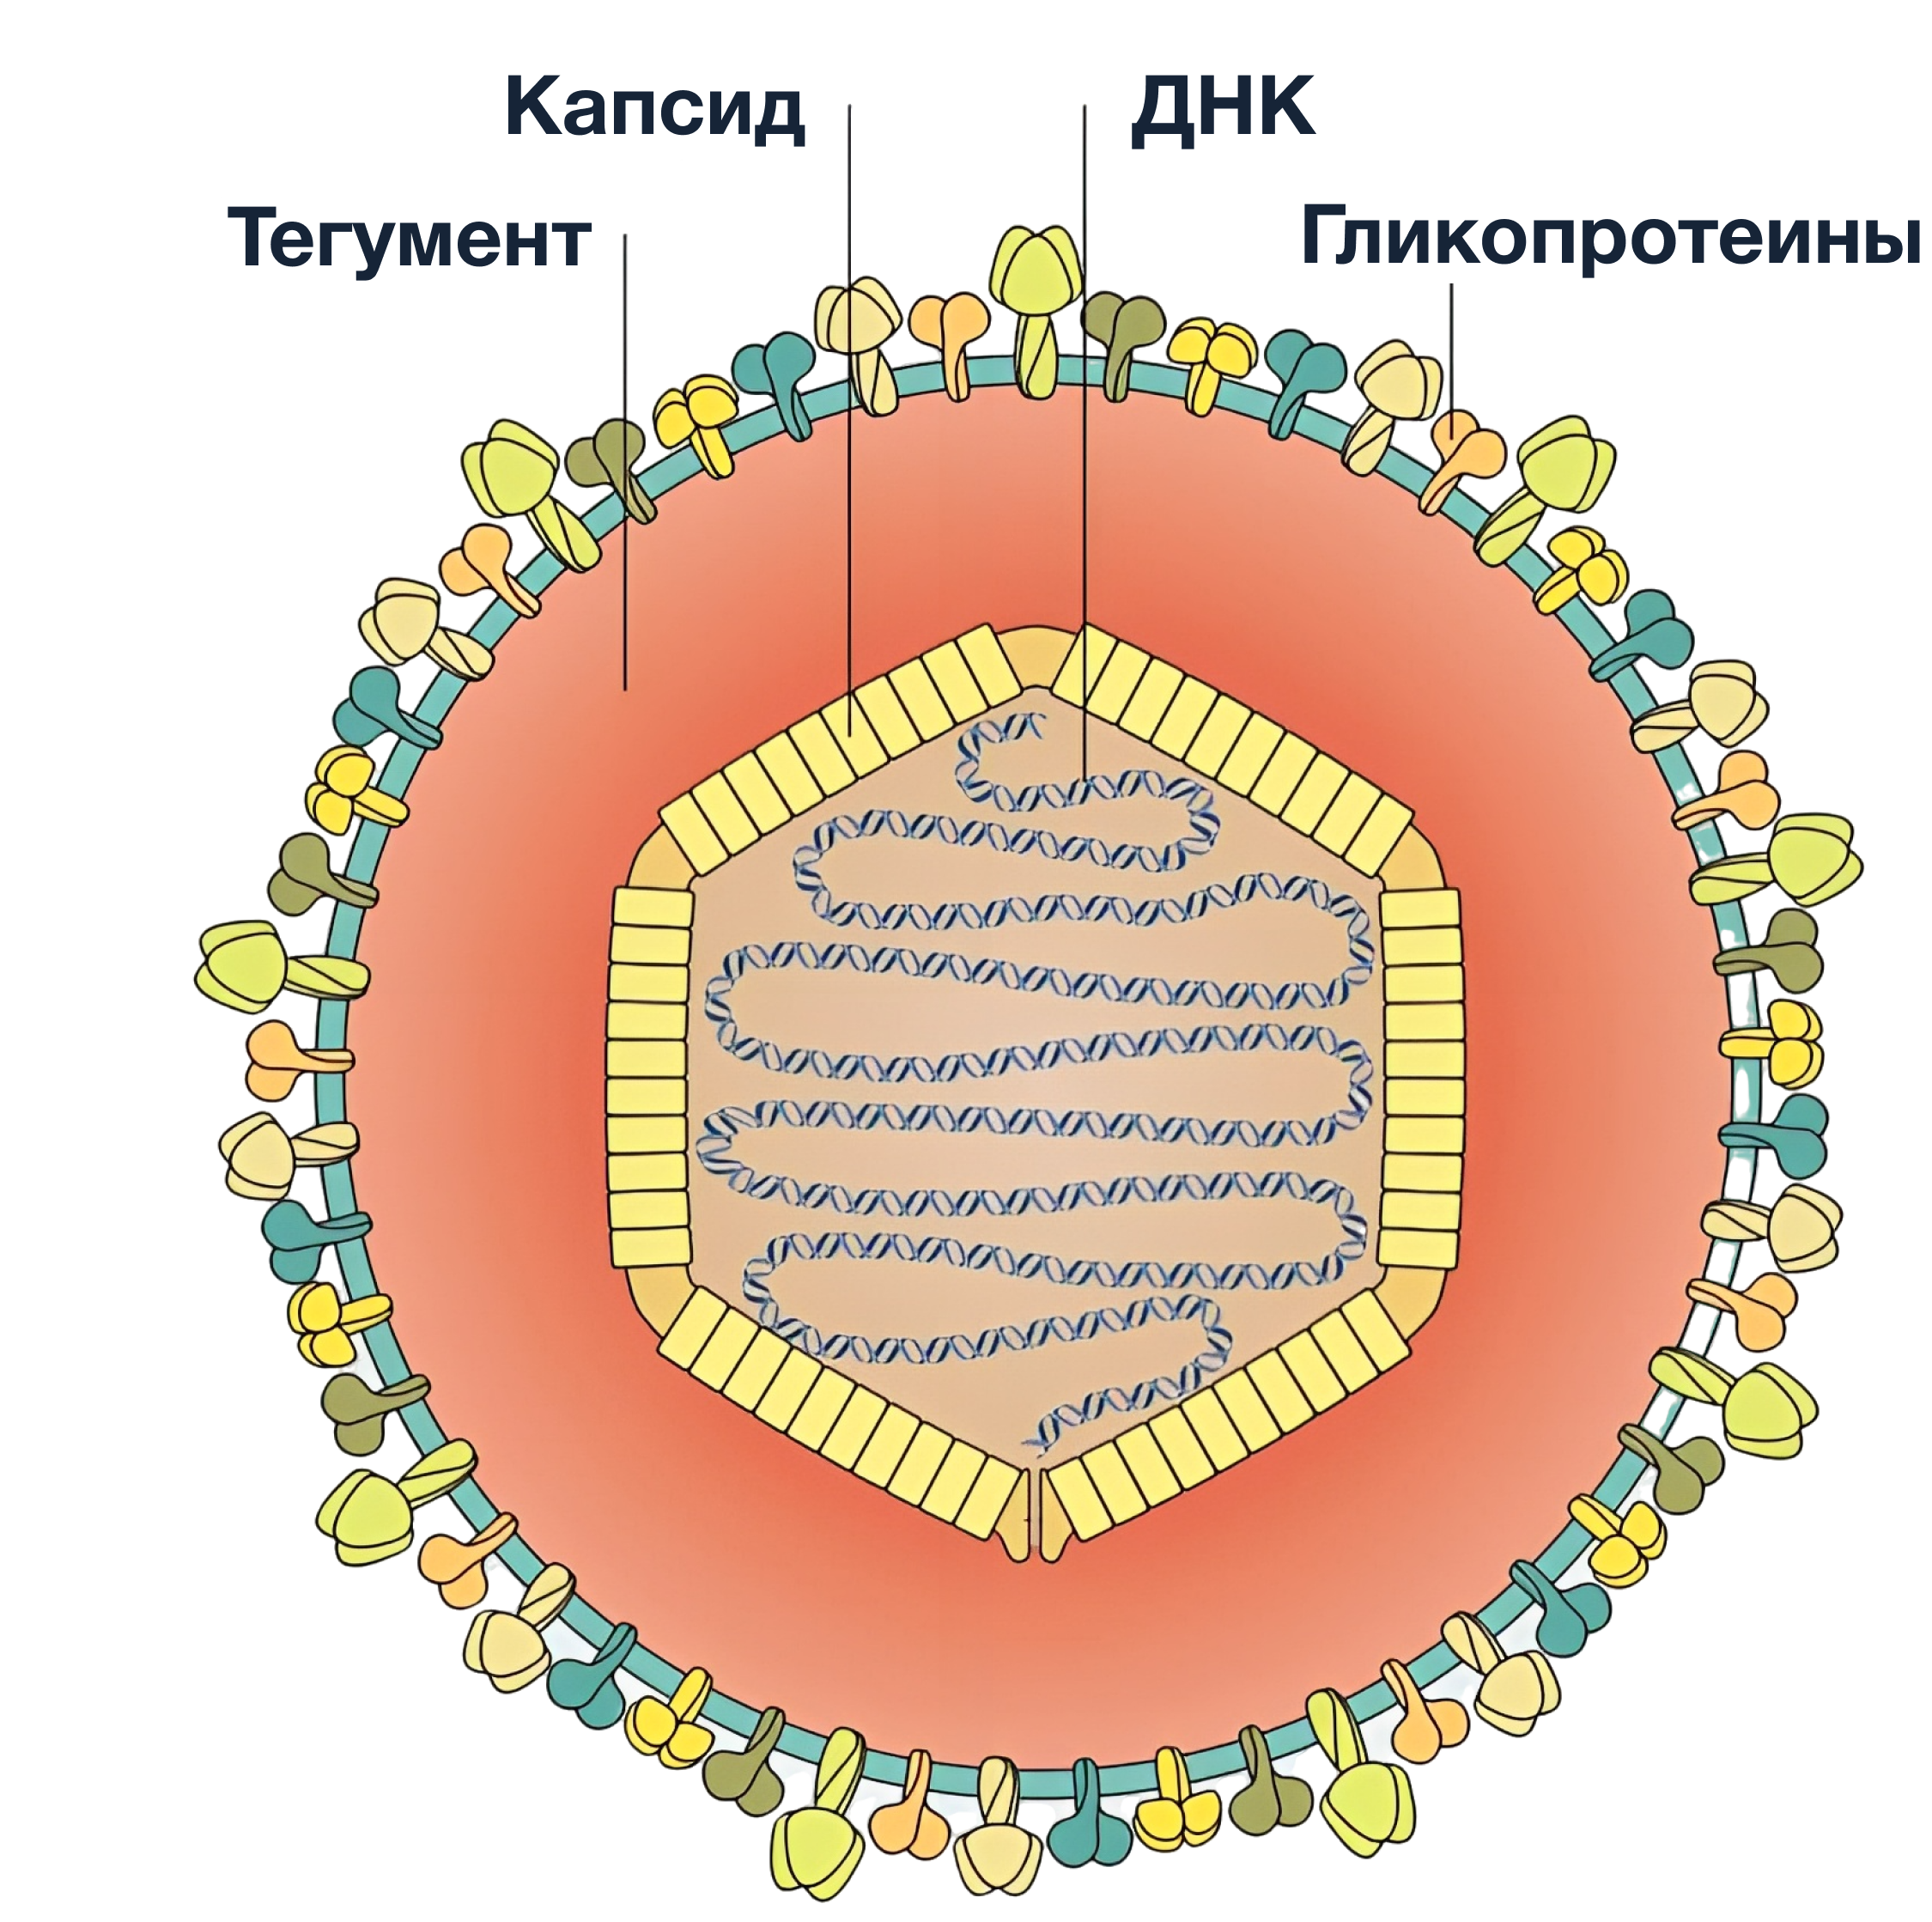

Медицинские снимки и изображения опоясывающего герпес вируса

Раздел: Фотодневник открытий